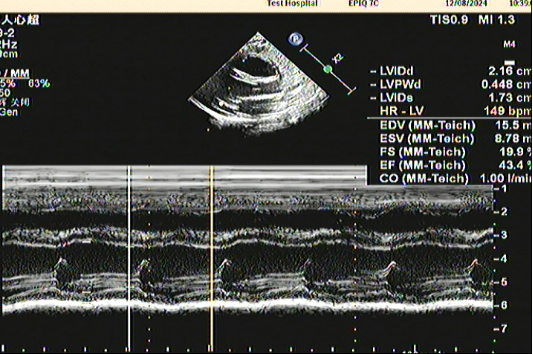

今日门诊就诊10天新生儿,口唇青紫发病,完善超声心动图提示:左室饱满,余房室腔内径测值正常范围。房间隔中部回声分离约2mm,室间隔连续完整。室壁心肌厚度及回声可;心内膜偏厚,回声偏强,室壁运动欠协调,收缩幅度减低。EF:45%。临床考虑心内膜弹力纤维增生症(EFE),那么心内弹是什么疾病呢?为什么会得这种疾病?有哪些表现?怎么诊断这个疾病?有哪些治疗方法?预后怎么样呢?带着这些疑问让我们走进心内膜弹力纤维增生症。心内膜弹力纤维增生是引起婴儿心力衰竭引起死亡的主要病因之一,占先天性心脏病的1%~2%,10%为家族性发病,男女发病均等,80%的患者发病年龄在3~6个月,病因不明确,可能与遗传、先天发育障碍、缺氧、妊娠早期服用某些药物和自体免疫等有关;也可能是宫内病毒感染如腮腺炎病毒、柯萨奇B病毒等感染或与心内膜下缺血、心脏淋巴回流受损、全身性肉碱缺乏症相关,此外基因突变与家族性X-连锁EFE相关。(1)暴发型:年龄多在6周内,突然出现心力衰竭、心源性休克,可致猝死;(2)急性型:年龄多在6周~6个月,起病较快,于1~2周加重,如未经适当治疗多在2~3周死于心力衰竭,少数可获缓解;(3)慢性型:发病稍缓慢,年龄多在6个月以上,进展缓慢,经治疗可获缓解而活至成年,亦可因反复心力衰竭而死亡。其中急性型为多,慢性型约占1/3。婴儿表现为气促、咳嗽、伴哮鸣的严重呼吸困难、喂养困难、多汗。暴发型者可突然出现呼吸困难、呕吐、拒食、口周发绀、面色苍白、烦躁不安、心动过速。肺部有喘鸣音或干啰音,肝大,水肿。少数出现烦躁、面色灰白、四肢湿冷、脉细弱等心源性休克表现。心力衰竭发生越早,病情越重,疗效越差,预后越差。20%~50%的患儿可出现各种心律失常,室颤是EFE患儿猝死的重要原因。由于心腔内多有附壁血栓形成,部分患儿左室栓子脱落引起体循环栓塞性病变偶尔右心栓子脱落栓塞肺动脉,引起肺梗死;栓塞冠脉可致心肌梗死;或引发脑血管事件、猝死。心脏超声检查对于心内膜弹力纤维增生症的诊断敏感性高,但特异性低。可见左室、左房内径扩大,左室内膜增厚、回声增强,室壁运动幅度普遍减低,房室瓣关闭不全,射血分数减低,二尖瓣活动异常。部分患儿可发现心腔内的血栓回声。主要目的为控制心力衰竭,防止病情进一步发展。(1)强心苷类:临床上可使用地高辛长期应用,一般需用药至症状消失后数年。定期观察,每2~4周调整1次剂量,长期使用应避免中毒。(2)血管紧张素转换酶抑制剂(ACEI):ACEI须从小剂量开始,逐渐增加,维持到心功能恢复。(3)利尿剂:对急性心力衰竭者可用呋塞米,利尿或口服氢氯噻嗪和螺内酯交替或联合使用,长期使用应注意水电解质平衡。(4)糖皮质激素:泼尼松可减轻心内膜、心肌的炎性反应有,并能改善心功能。一般1.5mg/(kg·d),6~8周减量,每隔2周将每日量减少1.25~2.50mg,当减至2.5~5.0mg/d时可持续维持1年以上。(5)其他治疗:急性加重常由呼吸道感染促发,应适当行抗感染治疗。贫血严重需输血纠正贫血;有栓塞者须抗凝治疗;还可以使用磷酸肌酸、二磷酸果糖等心肌营养药。据文献报道,EFE患儿经治疗1/3临床痊愈;1/3留有症状、心电图异常或心脏肥大的X线改变;1/3死亡,多为年龄小于6个月的婴儿,尤其是3个月内的小婴儿。有急性心力衰竭的婴儿如未接受心脏移植,则大多数死于急性发作。从出现症状开始心力衰竭反复发作超过6个月则预后不良。如果临床症状消失、无阳性体征,X线、心电图、超声心动图均正常,则认为临床痊愈。

心内膜弹力纤维增生症(Endocardial Fibroelastosis,EFE)一词最早由Weinberg和Himmelfarb 在1943提出,指大量胶原纤维和弹力纤维增生浸润,使心内膜弥漫性增厚,由正常的薄而透明变为瓷白不透明。临床上常表现为心力衰竭,多见于婴儿,但在儿童和成人也偶见报道。本病可单独存在,也可继发或并存于多种先天性心脏病,如:动脉导管未闭、左心发育不良综合征、主动脉瓣狭窄或闭锁、主动脉缩窄、左冠状动脉起源于肺动脉(ALCAPA)等。病理机制EFE的特征为心内膜弥漫性增厚和心功能降低。目前认为心内膜增厚是心肌受损或二尖瓣关闭不全导致长期室壁张力增高的结果,而且随年龄增长进行性加重。心内膜可弥漫增厚至1-2mm,呈乳白色、反光、不透明。心脏呈球形扩大,主要累及左心室和左心房。纤维化可累及乳头肌和腱索,乳头肌起源位置较高,腱索短粗,二尖瓣瓣缘卷曲,对合不良。50%的病例有二尖瓣或主动脉受累,引起瓣膜狭窄或关闭不全。心内膜表面可有微血栓附着。室壁厚度和冠状动脉内径大致正常。本病可能与病毒感染有关。1962年Fruhling等发现柯萨奇病毒流行后EFE的发病率明显增高,尸检可见单纯心肌炎、心肌炎合并EFE、心肌炎治愈后残留EFE的不同阶段,并且可在组织中培养出柯萨奇病毒。Noren等将腮腺炎病毒注射到鸡胚胎中,鸡最初表现为心肌炎,一年后出现典型的EFE,并且可见两者之间的不同阶段。Towbin等将腮腺炎预防接种年代之前的EFE尸检标本用现代遗传学的方法处理,80%的病例组织中可发现腮腺炎病毒的基因组。因此认为腮腺炎病毒经胎盘传播过去可能是EFE的主要致病原因,而且随着腮腺炎预防接种的开展,EFE的发病率显著下降。EFE也存在非感染性致病因素。本病可为常染色体或X染色体隐性遗传。G4.5基因(tafazzin)突变与EFE和Barth综合征相关,而且可引起妊娠18周胚胎心脏的形态改变。流行病学1964年美国EFE的发病率为1:5000,随后显著降低,其原因不明,目前认为与腮腺炎的患病率降低有关。1978年国外统计EFE约占所有先天性心脏病的1-2%。本病在发达国家已很罕见,但在我国并不少见。国内9省市心肌炎协作组统计本病约占全部住院患儿的0.3%。本病多为散发,家族病例可见于10%的患者。80%的病例发病年龄在生后3-6个月,确诊年龄常在生后2-12个月。性别方面无差异。临床表现本病临床上常表现为左心功能不全,主要症状包括呼吸急促、多汗、喂养困难、发育迟缓等。20%的患儿有反复或近期呼吸道感染的病史。本病也可引起心源性休克或猝死。本病的体征常有心脏扩大、第一和第二心音正常或减低、第三心音甚至奔马律、二尖瓣关闭不全的收缩期杂音、肝脾增大等。辅助检查1. 实验室检查除血常规、肝肾功能、电解质、心肌酶等常规检查外,可行病毒抗体和自身免疫性抗体检查,如抗-Ro和抗-La抗体。2. 心电图75%以上的患儿可见左室肥厚。生后数周内心电轴右偏和单纯右室肥厚更常见。年长患儿可有肺高压,心电图可表现为双室肥厚。5%的患者在病程早期心衰或终末期可有低电压。50%的患儿可有左房、右房或双房增大。ST段压低、T波倒置或低平也是常见的心电图表现。可能的心律失常包括预激综合征、左束支传导阻滞、室上性或室性心律失常以及不同程度的房室传导阻滞。3. 胸片主要表现为心脏扩大和肺静脉淤血。心影形态多样,但常为球形扩大,50%的患儿心胸比率超过0.65。心脏扩大可在生后出现,也可生后正常,数周或数月后才增大。25%的患儿由于左房扩大压迫左主支气管引起左下肺叶不张。4. 超声心动图超声心动图是EFE的主要诊断方法。可见左房左室增大、室壁运动低下、左室射血分数减低和不同程度的二尖瓣反流。左心室心内膜增厚、回声增强对诊断有重要价值。5. 核磁共振(MRI)MRI在EFE诊断中的价值近年来受到重视。MRI通过灌注和心肌延迟增强显像可确定EFE的存在。灌注显像时EFE表现为心内膜表面的一圈低强度信号,而心肌延迟增强显像时表现为高强度信号。6. 心内膜活检对于诊断不明确的病例可行心内膜活检。病理改变主要在心内膜,表现为胶原纤维和弹性纤维增生浸润。电镜还可见心内膜表面纤维蛋白沉积。心肌层大致正常,心肌有炎性改变的可称心内膜心肌病。诊断和鉴别诊断参考9省市心肌炎协作组的诊断标准:(1)早期(常在1岁以内,尤其是6个月以内)出现心衰,洋地黄治疗有效,但病程较长,常有反复;(2)杂音一般较轻或无,II级以上的收缩期杂音提示二尖瓣关闭不全;(3)胸片示肺淤血和心影增大,以左心为主;(4)心电图示左室肥厚,ST-T改变,少数病例有心律失常;(5)超声心动图发现心内膜改变和心功能降低可提供最重要的诊断依据;(6)排除其他的心血管疾患。 本病需与左冠状动脉起源于肺动脉(ALCAPA)、糖原累积症等疾病鉴别。心电图I、avL、V4-V6出现异常深宽Q波伴T波倒置高度提示ALCAPA,超声心动图的特征包括右冠状动脉与主动脉根部内径的比值超过0.20、左冠位置未见血管或正常血流、室间隔见侧支血流、乳头肌回声增强,肺动脉瓣上见汇入肺动脉的红色血流束。治疗EFE的治疗主要针对慢性心功能不全。地高辛可增加心肌收缩力,减慢心率,抑制交感神经。血管紧张素转换酶抑制剂(ACEI)可降低后负荷,改善左室重构。呋噻米、螺内酯是临床上常用的利尿剂。早期应用上述药物并长期维持治疗可改善患儿的预后。β-受体阻断剂可改善成人心衰的临床预后, 在儿童疗效仍在观察中。病情较重或治疗效果不满意时可加用丙种球蛋白、糖皮质激素或免疫抑制剂治疗。出现血栓栓塞并发症时应予抗凝治疗。预后早期诊断和长期维持治疗对于EFE的预后至关重要。有学者认为1/3的患者可完全治愈并停药。北京安贞医院的5年治愈率为56.1%,10年治愈率为73.1%。预后不良的指证包括(1)新生儿期即有心衰表现;(2)积极治疗后仍反复发作心衰。 参考文献[1] Weinberg T, Himmelfarb AJ. Endocardial fibroelastosis. Bull Johns Hopkins Hosp. 1943;72:299.[2] 吴邦俊,王惠玲. 婴儿心内膜弹力纤维增生症. 见:杨思源主编. 小儿心脏病学. 第三版. 北京:人民卫生出版社,2005,424-427.[3] 焦萌,韩玲,王惠玲,等. 原发性心内膜弹力纤维增生症75例远期疗效. 中华儿科杂志. 2010;48(8):603-609.[4] Zheng JY, Han L, Ding WH, et al. Clinical features and long-term prognosis of patients with anomalous origin of the left coronary artery from the pulmonary artery. Chin Med J (Engl). 2010,123(20):2888-2894. ( 韩玲 )

心内膜弹力纤维增生症(endocardial fibroelastosis)。其主要病理改变为心内膜下弹力纤维及胶原纤维增生,病变以左心室为主。多数于1岁以内发病。原因尚未完全明确,部分病例可能由病毒性心肌炎发展而来;心内膜供血不足及缺氧亦很可能为发病的原因,约9%病人有遗传倾向。原发性心内膜强力纤维增生症没有明显瓣膜损害和其他先天性心脏畸形。而继发性心内膜弹力纤维增生症有左心梗阻型的先天性心脏病如主动脉缩窄、左心发育不良综合征及主动脉瓣闭锁或狭窄。 【临床表现】主要表现为充血性心力衰竭,按症状的轻重缓急,可分为三型。 1.暴发型 起病急骤,突然出现呼吸困难、口唇发绀、面色苍白、烦躁不安、心动过速、心音减低,可听到奔马律,肺部常听到干、湿哕音,肝脏增大,少数出现心源性休克,甚至于数小时内猝死。此型多见于6个月内的婴儿。 2.急性型 起病亦较快,但心力衰竭发展不如暴发型急剧。常并发支气管炎,肺部出现细湿哕音。部分患者因心腔内附壁血栓的脱落而发生脑栓塞。此型发病年龄同暴发型。如不及时治疗,多数死于心力衰竭。 3.慢性型 症状同急性型,但进展缓慢。患儿生长发育多较落后。经适当治疗可获得缓解,存活至成年期,但仍可因反复发生心力衰竭而死亡。【诊断】1.心电图 多呈左心室肥大,少数表现右心室肥大或左、右心室合并肥大,广泛ST段水平下移、T波倒置。2.胸部X线 以左心室肥大为明显,左心缘搏动多减弱,肺纹理增多。3.超声心动图 左心室明显扩大、二尖瓣与三尖瓣返流,心脏收缩与舒张功能均减低,心内膜回声增强且增厚是本病的典型特征。【治疗】主要应用地高辛、利尿剂、ACEI控制心力衰竭,强的松抑制免疫,一般反应较好,需长期服用,直到症状消失,X线、心电图恢复正常后1至2年方可停药。合并肺部感染时,应给予抗生素等治疗。本病如不治疗,大多于半岁前死亡。对洋地黄治疗效果好而又能长期坚持治疗者,预后较好,且多数能痊愈。